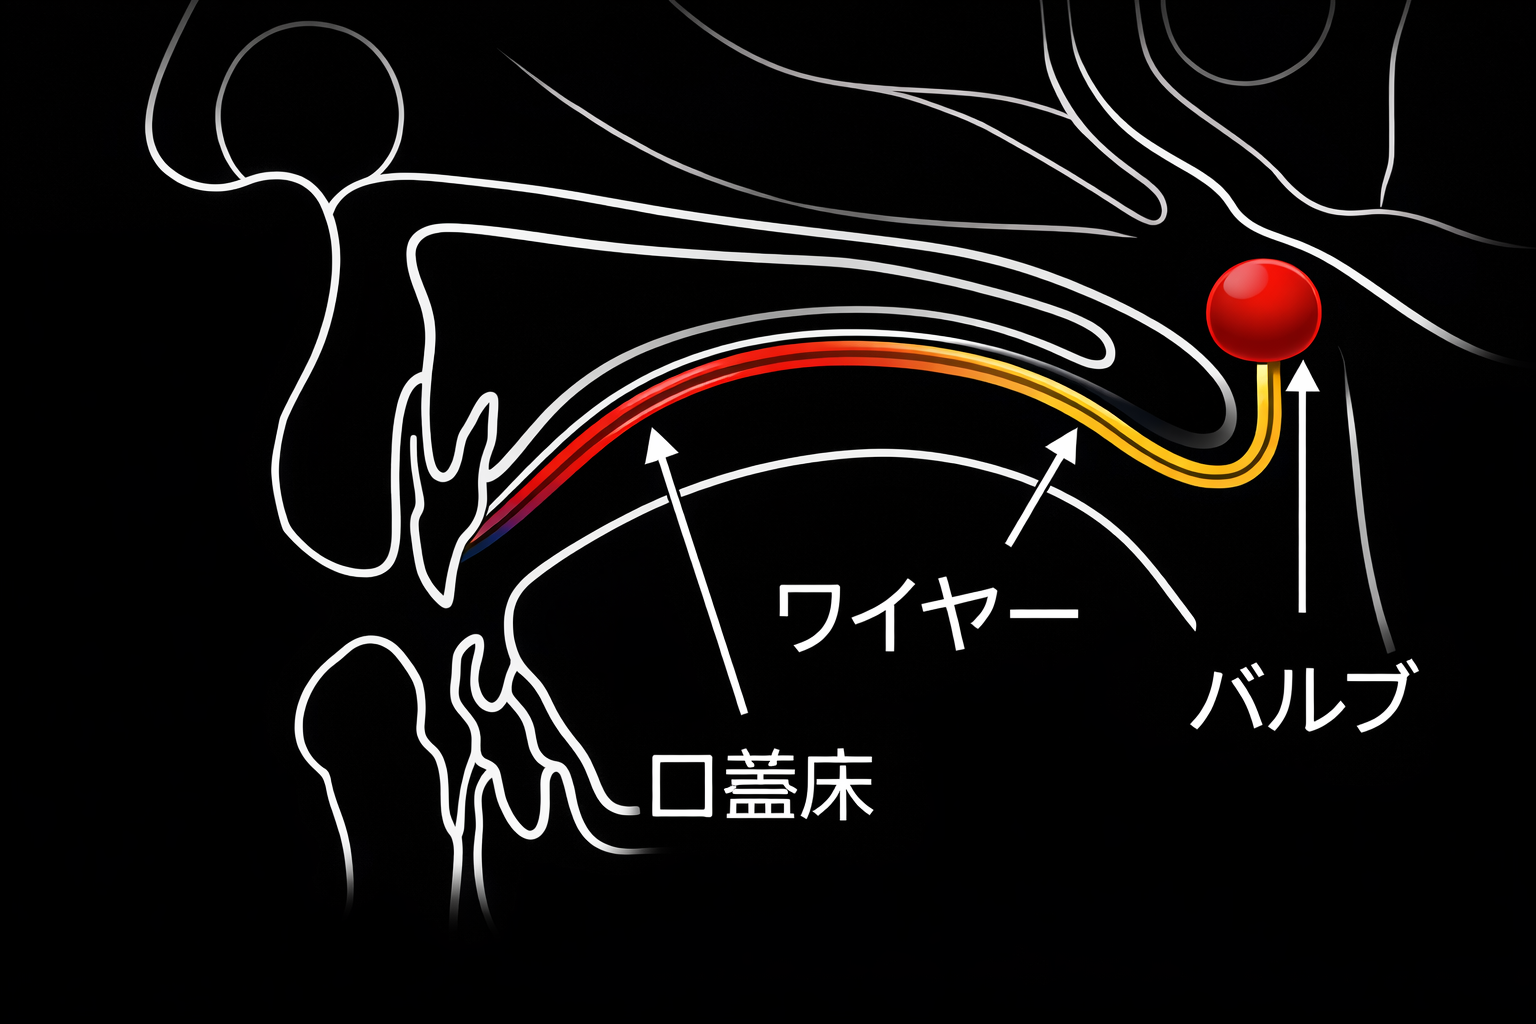

スピーチエイドとは

スピーチエイドは、口と鼻の奥をうまく閉じられない「鼻咽腔閉鎖機能不全」を補い、発音や食事をスムーズにするための装置です。入れ歯や矯正装置の後ろに突起状のバルブが付いており、上あごに装着して使用します。装置の先端には、バルブという突起状の膨らみがあり、これが喉の奥の隙間をふさぐ役割をします。これにより、話すときに鼻から息が漏れるのを防ぎ、言葉がはっきりと相手に伝わりやすくなります。また、飲み物が鼻に逆流するのを抑える効果もあります。

スピーチエイドは、喉の奥がうまく閉じない「鼻咽腔閉鎖機能不全」のうち、一部の方が対象となります。具体的には、口蓋裂の手術後も発音が改善しにくい方や、腫瘍の摘出手術で咽頭の一部を失った方です。またこれら以外にも、言葉が鼻に抜けたり、飲み物が鼻へ逆流したりする方に有効な場合もありますので、専門医の診断を受けてください。

鼻で息をする時には、喉の奥と鼻は空気が通る状態になっていますが、発音を行ったり、食べ物を飲み込んだりするときは、鼻に逆流しないように、鼻と喉の奥をふさぐ(鼻咽腔閉鎖といいます)必要があります。この機能を果たしているのが「軟口蓋」ですが、この組織の大きさが生まれつき足りなかったり、腫瘍の手術などで失った場合に、その足りない部分を補うことを目的とする装置です。

言葉を話す時に、鼻から抜けてしまうような発音になることを防いでくれたり、食事の際に食べ物や飲み物が鼻に逆流してしまうことを防ぐ効果があります。